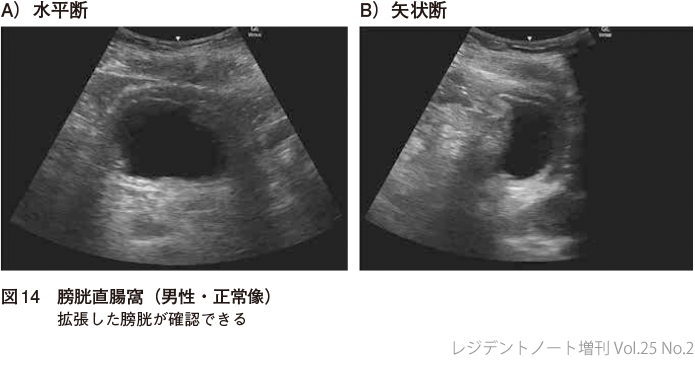

2確認するポイント

1)膀胱直腸窩(男性)

膀胱,前立腺,直腸(通常は壁しかみえない)を同定し膀胱直腸窩に液体貯留があるかどうか確認する(図14,15).